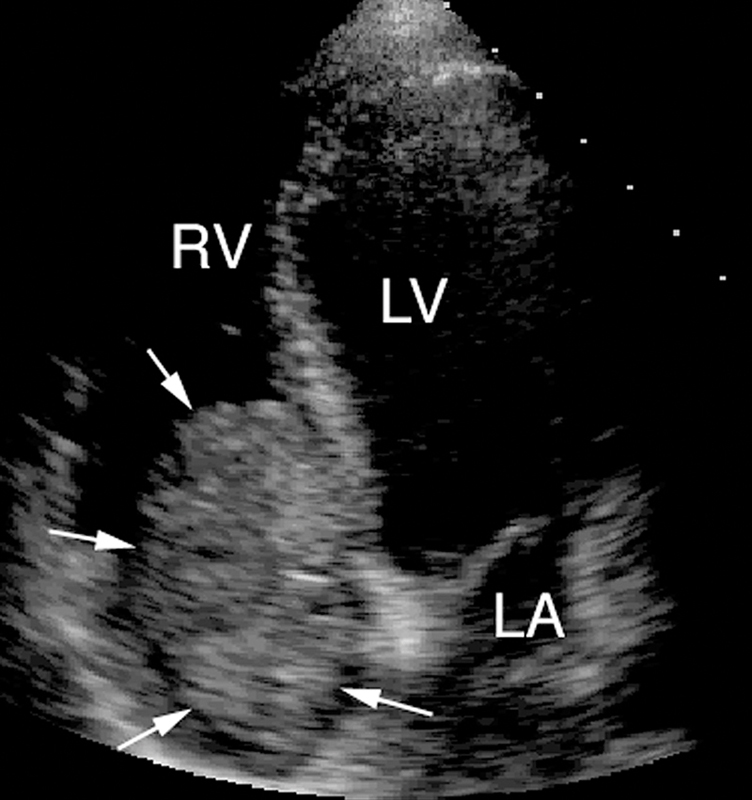

فحوصات تشخيصية لبعض امراض القلب والشرايين التاجية